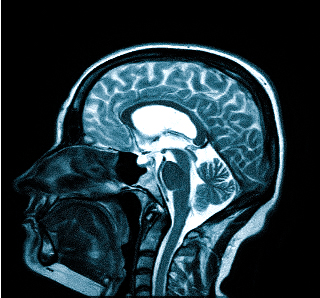

Процедура МРТ при головных болях

- МРТ (магнитно-резонансная томография) — это процедура, которая дает полное представление о состоянии исследуемой части тела пациента, а также о наличии или отсутствии того или иного заболевания. При МРТ четкие снимки получаются за счет обследования организма человека посредством воздействия магнитного поля.

Как проводится МРТ головного мозга?

Для проведения процедуры пациент ложится на стол-транспортер, который заезжает в томограф — сканирующее устройство. На время обследования пациент остается в трубе и должен сохранять неподвижность, чтобы картина получилась четкой. Процедура может занимать разное время — от 15 минут.

МРТ при головных болях (в трех проекциях): специальная программа выстраивает объемные изображения полученных срезов, что позволяет увидеть даже мельчайшие изменения и отдифференцировать патологию от нормы